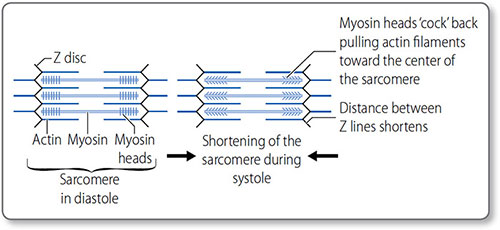

Myocytes contain elongated myofibrils composed of functional units called sarcomeres (Figures 1.25 and 1.26). Each sarcomere is bounded at each end by a Z line and contains contractile filaments made of the proteins actin and myosin. Peripherally, actin thin filaments attach to the Z line. Centrally, myosin thick filaments interdigitate (i.e. overlap) with the actin filaments.

Figure 1.25: The sarcomere. (a) The sarcomere is bound by the Z lines – formed by the arbed ends of thin actin filaments. The filaments project centrally, where they interdigitate with thick myosin filaments. This gives the striated appearance of cardiomyocytes, defined by the M line, the H zone and the A and I bands. (b) Actin−myosin interaction.

Figure 1.26: Sarcomeres and the sliding filament mechanism of myocardial contraction. Within the sarcomere, the central thick myosin filaments are surrounded by the thin actin filaments. Contraction of the many myocardial sarcomeres underlies contraction, and causes the H band to disappear, the A band to increase and the I band to shorten.

The sliding filament model of contraction The myosin ‘power stroke’ pulls the filaments so that they slide in opposite directions; this sliding shortens the sarcomere and in turn contracts the myocardium. Cycles of myosin-head binding to actin, contracting, disconnecting and then reattaching – a ‘ratcheting’ effect – progressively shorten the sarcomere as long as intracellular Ca2+ remains high. Both contraction and relaxation are energy dependent 39(ATP consuming). In the heart this is a continual cycle hence the large concentration of mitochondria and glycogen stores.